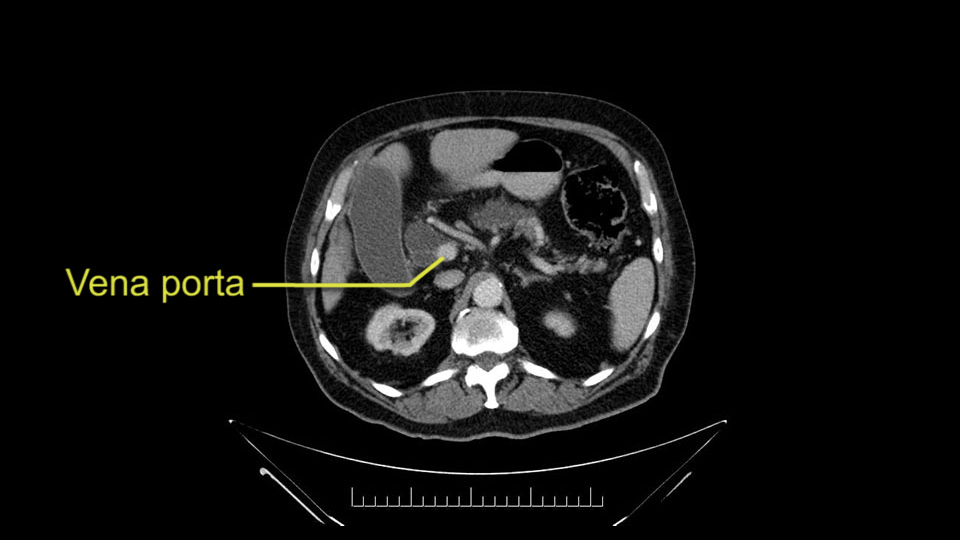

The next item that I would look at: the issue would be the vessels and usually start at the portal vein, watch the portal vein, follow it down, down-down-down to the neck of the pancreas - which is here - and there’s no impingement by tumor, which is great. The SMV and the splenic vein, which is here. The splenic vein junction is normal, which is great.

The next thing we always evaluate, although we do not expect invasion to the portal veins in this case, we must always trace the path of the portal vein, in both directions, from top to bottom. The splenoportal confluence and the superior mesenteric vein, which in this case does not appear to be compromised.

Por otro lado, siempre evaluamos -aunque en este caso no esperamos que haya invasión de los vasos portales-, siempre hay que hacer el recorrido de la vena porta, en ambos sentidos, de arriba hacia abajo; el confluente esplenoportal y la vena mesentérica superior, que en este caso no aparentan estar comprometidos.

The first steps of a pancreaticoduodenectomy involve ensuring the CT findings are correct: exploring for signs of metastatic disease, peritoneal implants involving the omentum or the undersurface of the diaphragm and if again this is confirmed exploration that there's no metastatic disease, I begin the mobilization and really determining the relationship of the tumor with the major visceral vessels. I start by an extended Kocher maneuver, identify the superior mesenteric vein below the neck of the pancreas. They’re very thin walled vessels and as you're dissecting you have to use the ultimate care and meticulously dissect the superior mesenteric vein, ligate the anterior branches and begin the dissection from below to under the neck of the pancreas. At this point, if there's no reason to be concerned about whether there is any vascular invasion below, I usually take the gallbladder down. I mobilize the common hepatic duct above the insertion of the gallbladder. This patients already has a stent in place. So I would divide the bile duct at this point. This facilitates the dissection of the anterior surface of the portal vein and as I would expect looking at this imaging that there is nothing to be concerned about in terms of vascular involvement.